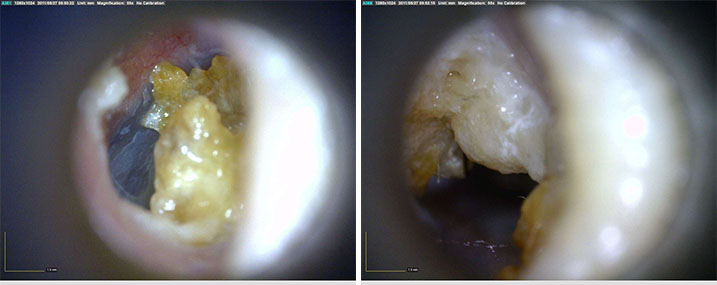

AF4113-EUT

產品參數(shù)

效果展示